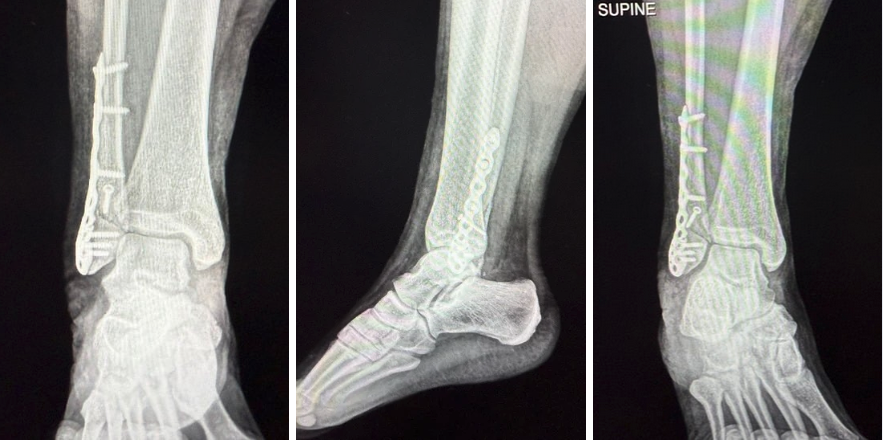

Fixation included a single lag screw to stabilize the long oblique fracture. A 3-hole distal anatomical fibular plate provided neutralization. Two bicortical screws inserted into the fibular shaft secured the plate proximally, and 3 locking screws affixed the distal fragment. Fluoroscopy allowed for verification of all screw positions.

Following thorough irrigation, the surgeon confirmed hemostasis after tourniquet deflation. Layered closure was with 2-0 Vicryl for the deep tissues, followed by 2-0 Vicryl for the subcutaneous layer and nylon for the skin. Application of a sterile dressing and immobilization with a CAM boot concluded the case.

As a podiatric physician participating in the procedure, I observed the technique and decision-making involved in distal fibular fracture fixation from the orthopedic trauma perspective. Notably, I felt that the use of a neutralization plate combined with both bicortical and locking screws reflected a thoughtful approach to optimizing stability in an active, weight-bearing adult.

I observed that the fracture exposure was efficient and well-controlled, allowing clear visualization for reduction. Bicortical lag screws provided compression across the fracture site, while locking screws reinforced fixation in distal segments with less bone stock.

The combination of construct mechanics appeared offer a reliable method to protect against rotational and shear forces during the early postoperative phase. This surgical experience provided valuable insights into fixation principles applicable to a range of foot and ankle procedures, particularly in managing trauma in otherwise healthy adults.